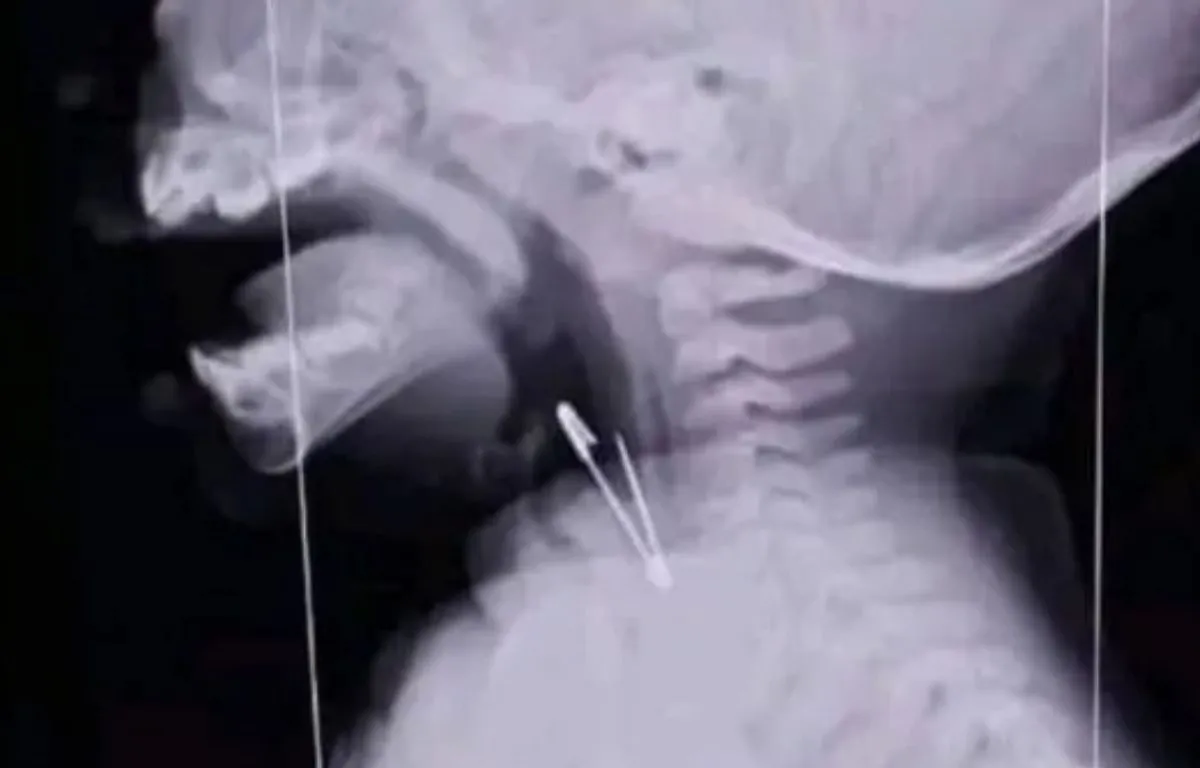

Un conmocionante hecho ocurrió en una escuela de Tartagal. Un niño de tan sólo 9 años se tragó un alfiler de gancho y tuvo que ser inmediatamente hospitalizado de urgencia debido a la gravedad del caso. Afortunadamente los médicos pudieron estabilizar al chico, aunque la radiografía que se le realizó generó un verdadero impacto en toda la comunidad educativa.

Como se ve en la radiografía a la cual accedieron los medios de comunicación, el objeto punzante se alojó en la zona de la laringe, lo que implicó un trabajo prácticamente artesanal para retirárselo sin poner en peligro su vida cuidando cada músculo de su garganta.